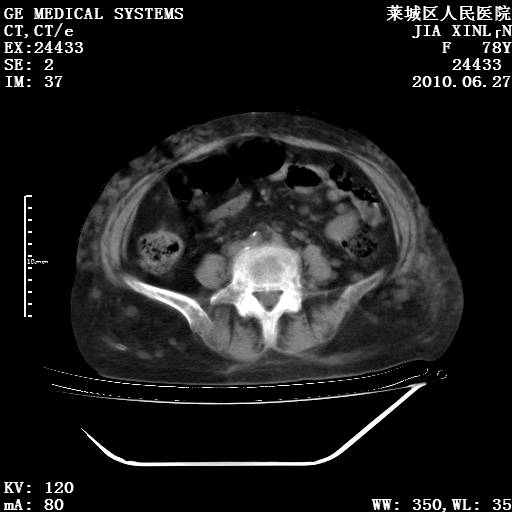

以下是引用胡宇在2010-7-2 19:11:00的发言:[br]神经纤维瘤的特点为:肿块呈多发性、数目不定,少的几个,多的可成百上千难以计数。小的如米粒,大的似拳头,甚至可达十数公斤以上。可松弛地悬挂于皮表,皱褶及松弛可致畸形明显。神经纤维瘤沿神经干的走向生长时呈念珠状,或蚯蚓块状形结节。此外神经纤维瘤皮肤可出现咖啡斑,大小不一,形如雀斑小点状,或大片状,分布与神经纤维瘤肿块的分布无关。肿瘤数目不多的患者,皮肤色素咖啡斑状沉着是纤维神经瘤的重要诊断之一。 本病多发于躯干,有时出现于四肢及面部,患者常合并许多疾病应予重视加以区别。 [br] [br] [br] [br]lyb999说 [br]